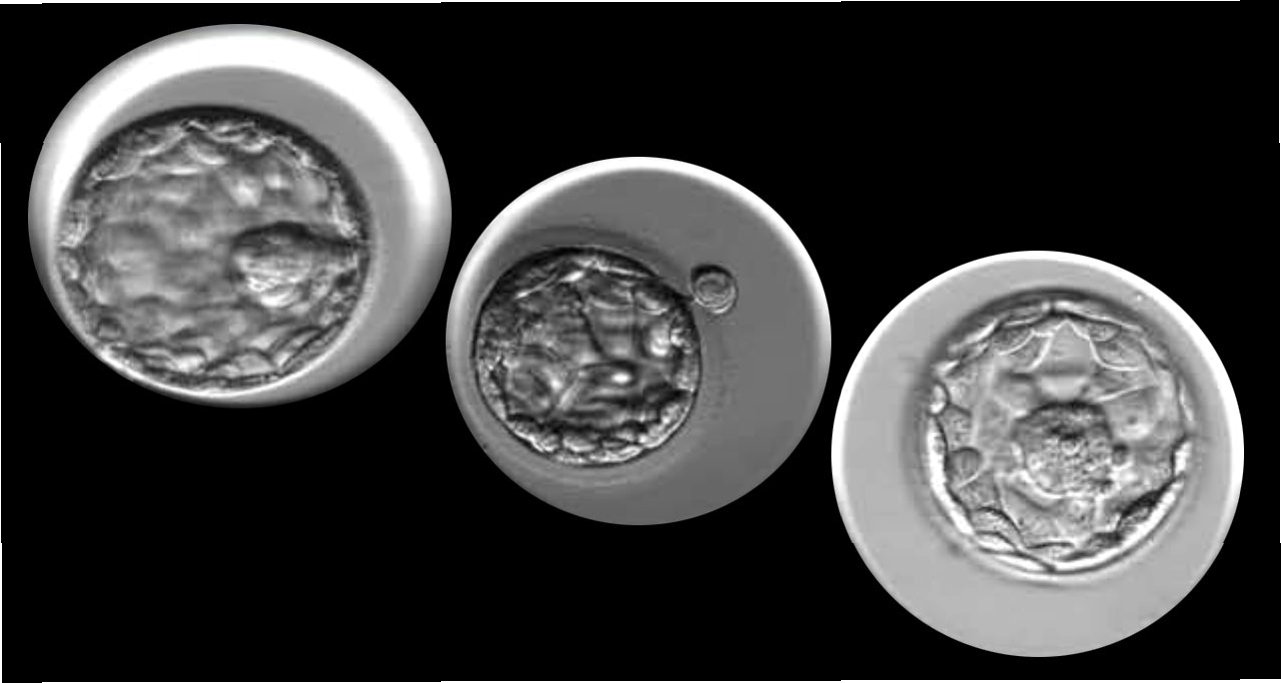

4. 배아 배양: 수정된 난자가 잘 분열하여 배아로 성장하도록 배양합니다. 배아의 질은 임신 성공률에 큰 영향을 미치므로, 배양 환경이 매우 중요합니다.

5. 배아 이식: 가장 건강한 배아를 선택하여 자궁 내막에 이식합니다. 이식 과정은 비교적 간단하며, 통증이 거의 없습니다. 이식 후에는 착상을 돕기 위해 황체 호르몬 보충 주사를 투여합니다.